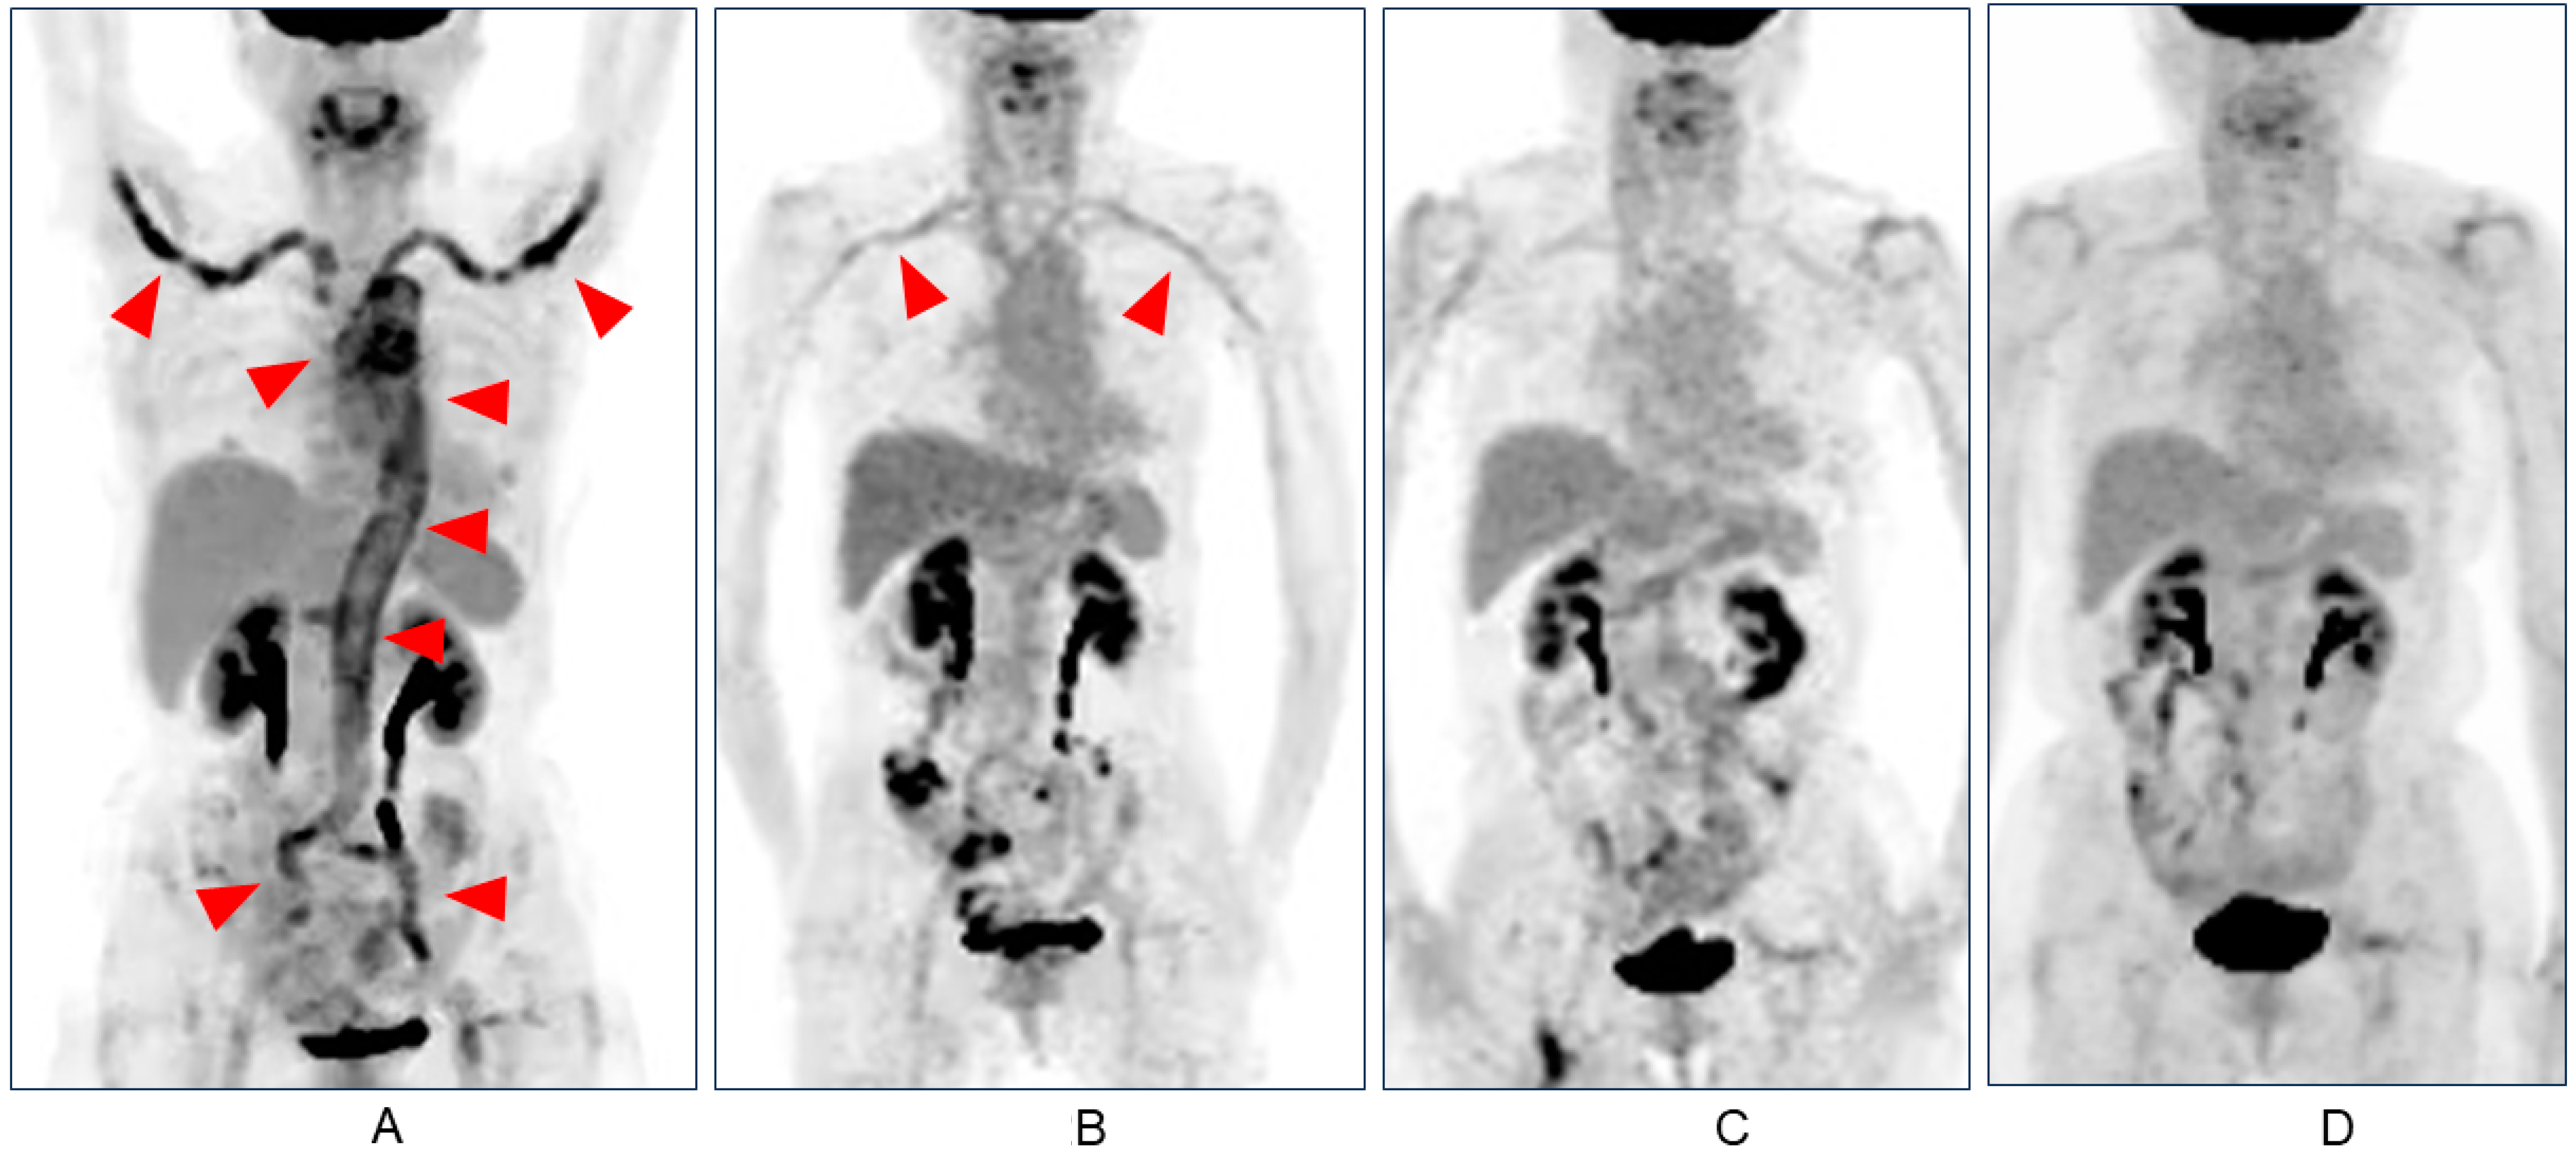

| Yoshimoto et al. (this case) | F, 69 | None | Headache, fever, abdominal pain, body weight loss | mRNA | 1 | 2 days | 38 days (5 weeks) | PET | GCA | LV-GCA | Ascending aorta, aortic arch, descending aorta, bilateral subclavian and iliac artery (PET) | 211 | 140 | 1g mPSL pulse PSL 50 mg TCZ 162 mg | 2 weeks | 2 years | Discharge (Remission with PSL 3 mg & TCZ) |